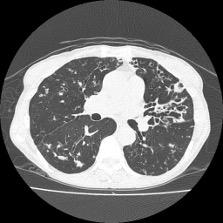

- X光肺片或電腦掃描檢查

- 常見肺部放射線學的變化

- 結節支氣管擴張